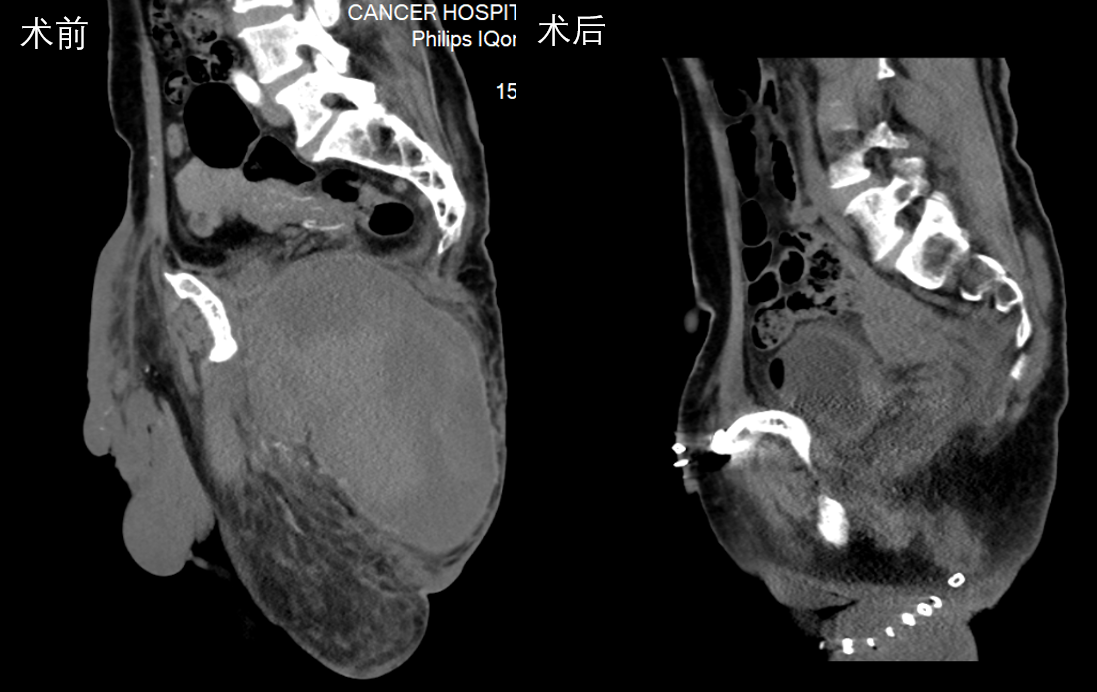

患者21岁女性,因左下腹隐痛2月,检查发现左腰骶椎前占位4天来诊。入院后进一步完善影像学检查提示左侧L5/S1椎间孔及椎体前后方占位。病灶钻缝生长,延伸至椎管内,再沿L5左侧横突孔向后伸至脊柱旁,横突孔增宽增大,骨质变薄,邻近肠管、左侧髂总血管稍推压移位。穿刺活检结果提示神经鞘瘤。

图片 7.png

图片 8.png

因肿瘤成哑铃状跨越椎体前后方,手术需行前后联合入路,前方入路需面对髂血管、输尿管等重要结构,后方则有脆弱的脊髓及神经根,对手术技巧要求极高,并且需要手术医生掌握大量的解剖学知识。经过充分的术前准备及术中的精细操作,完整切除肿瘤并重建脊柱稳定性。术后患者下肢功能未受影响,复查腰椎正位片示内固定稳定在位,CT示肿瘤已完整切除。